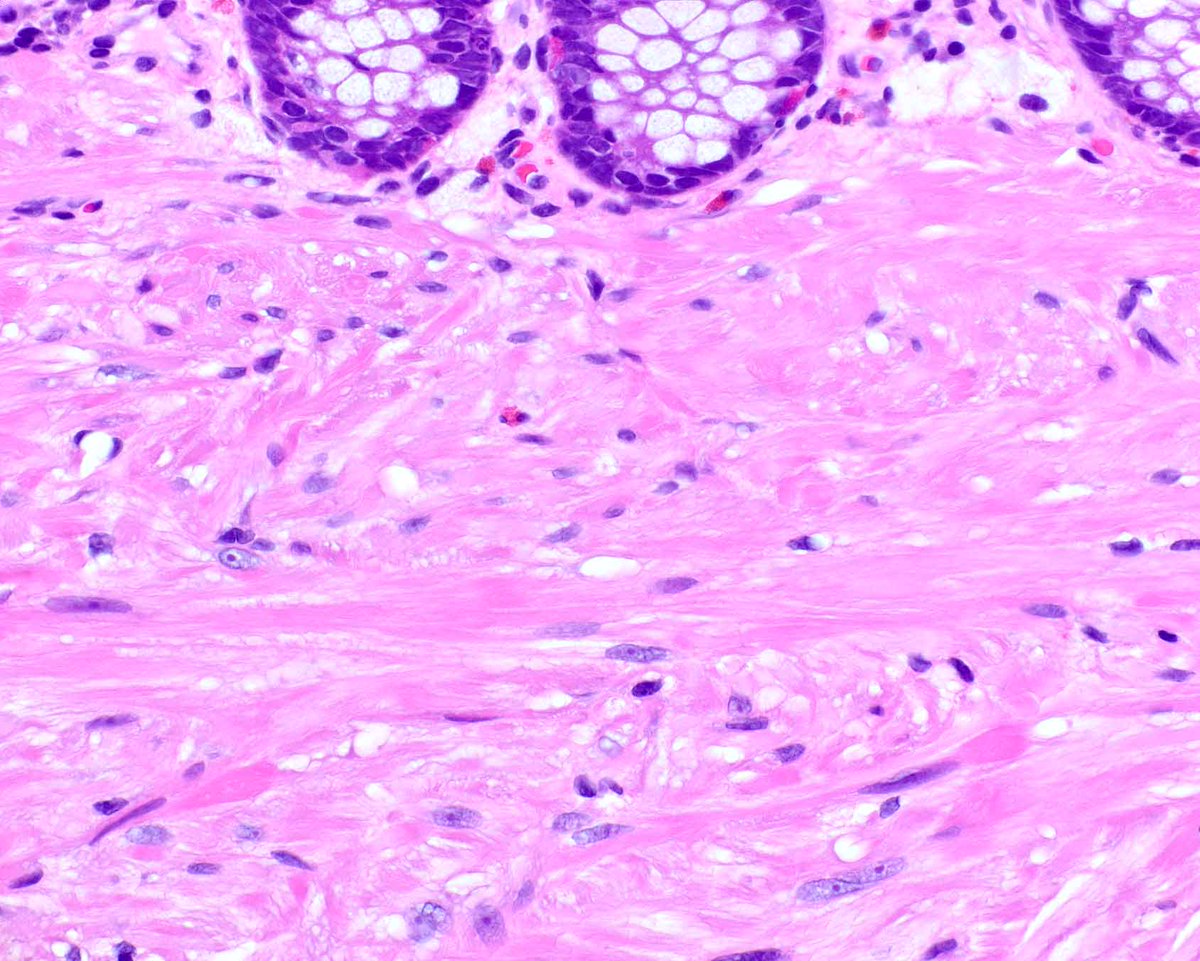

ISGyP 167.3; 56 years, Cervix. Diagnosis: NTRK3-rearranged sarcoma. NTRK-rearranged sarcoma of the cervix is rare characterized by specific genetic rearrangements (NTRK1 or NTRK3 fusions) that make them responsive to targeted therapy with tropomyosin receptor kinase inhibitors.

Diagnosis: NTRK3-rearranged sarcoma. NTRK-rearranged sarcoma of the cervix is rare characterized by specific genetic rearrangements (NTRK1 or NTRK3 fusions) that make them responsive to targeted therapy with tropomyosin receptor kinase inhibitors.